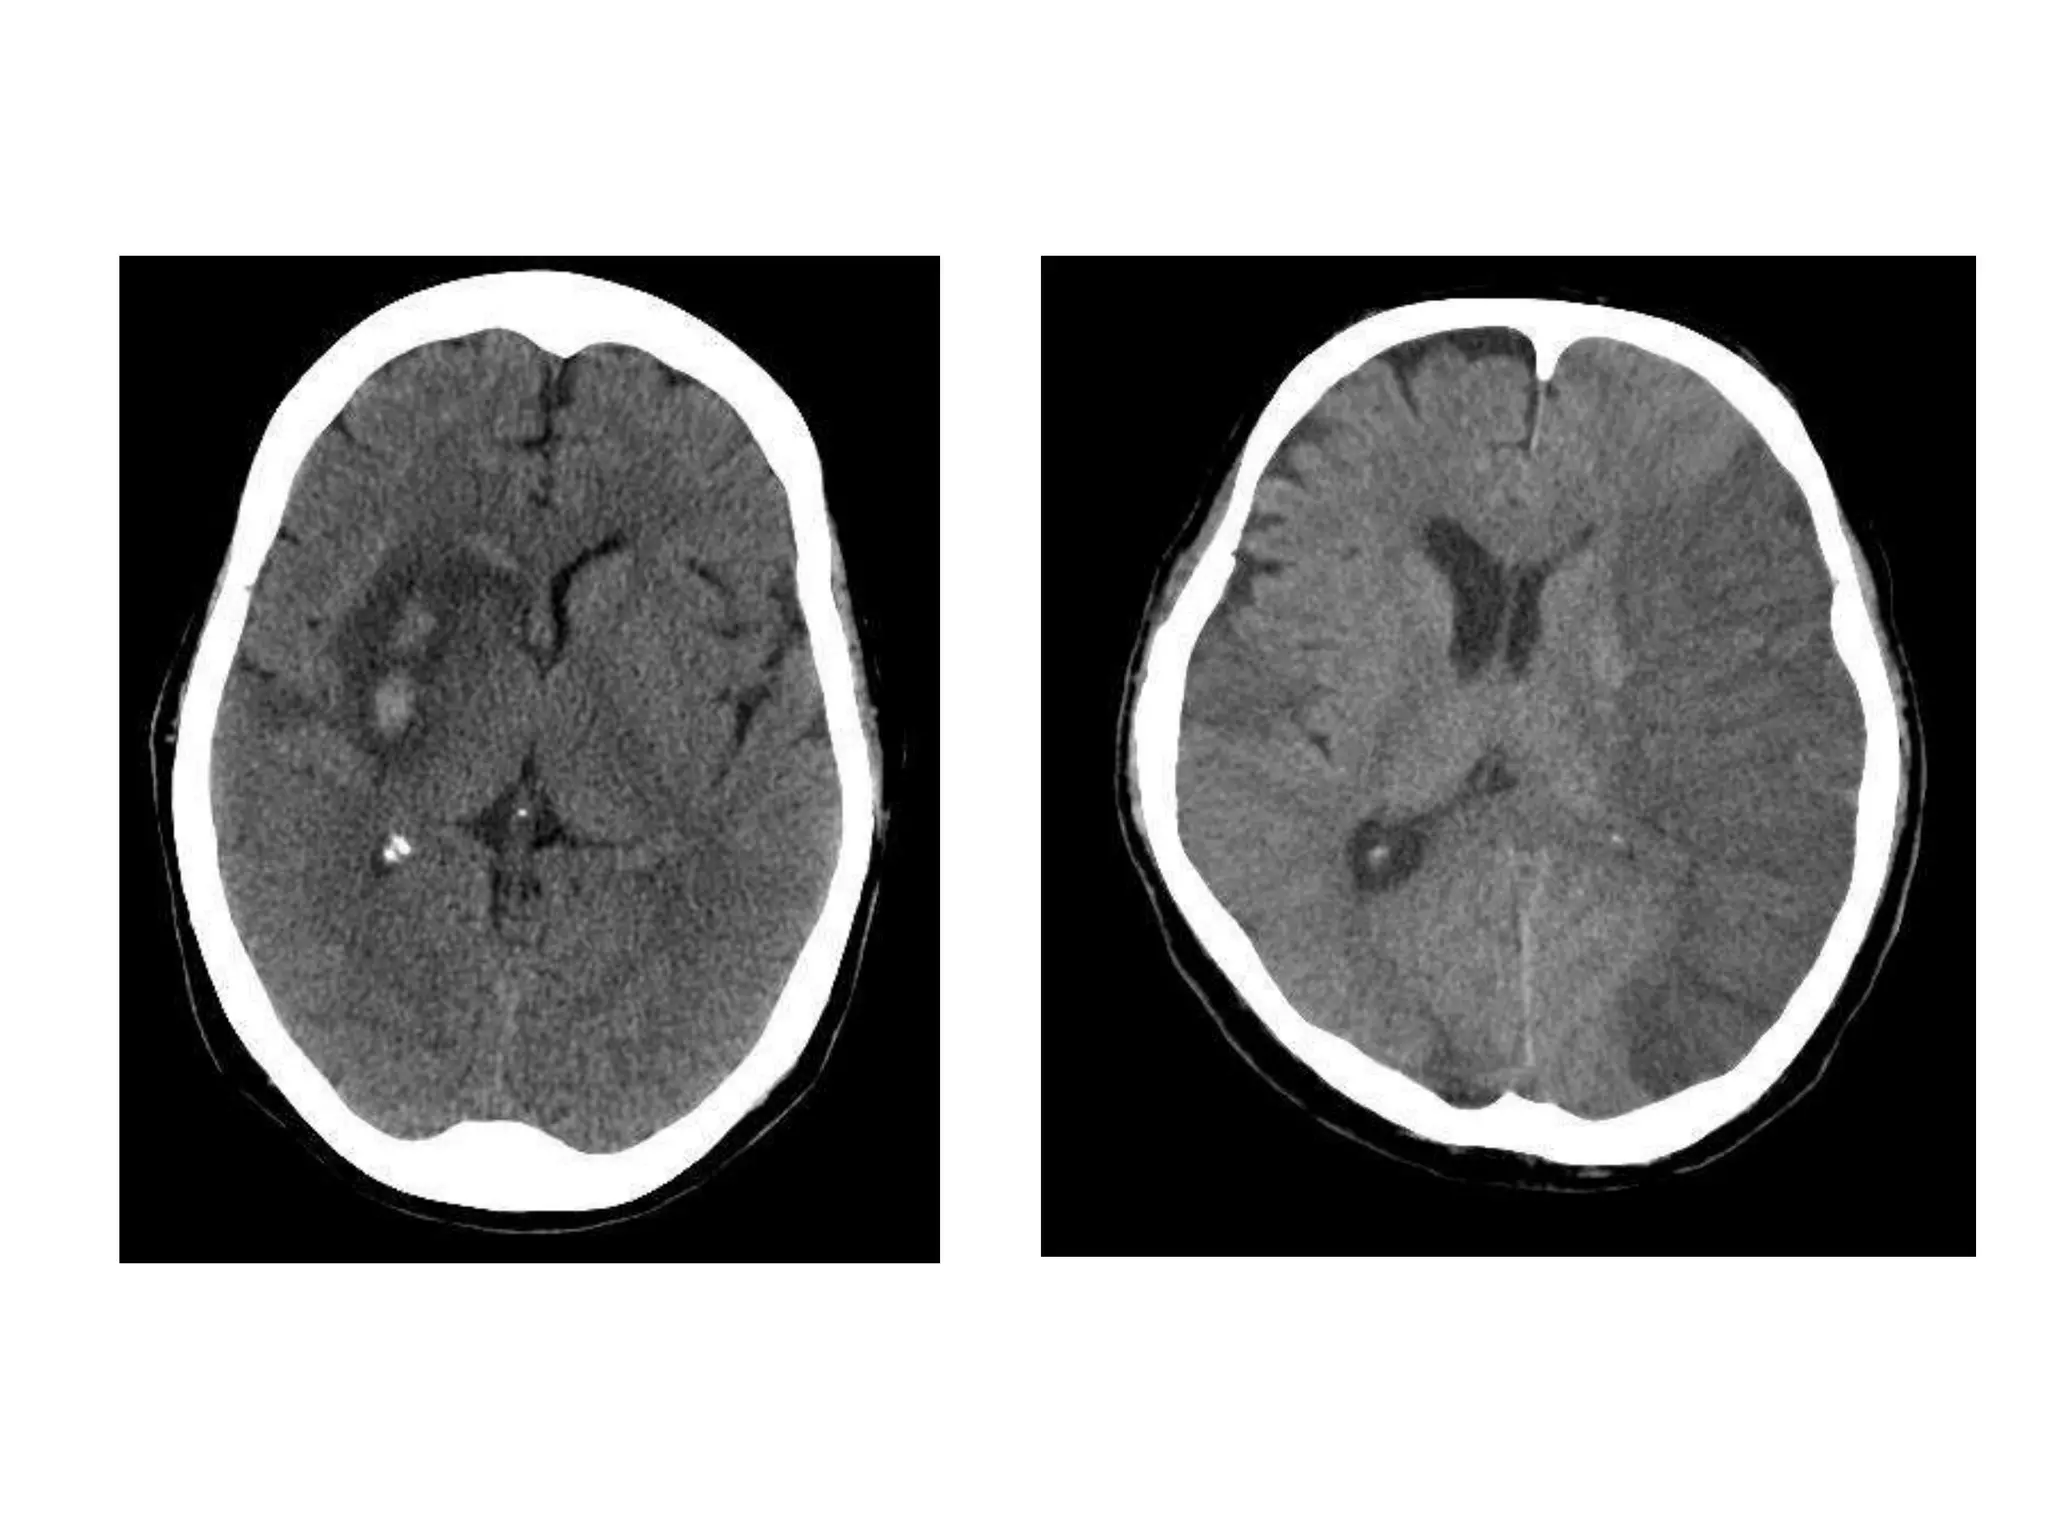

• #12 Hemorrhagic, Ischemic

• #13 Hemorrhagic conversion